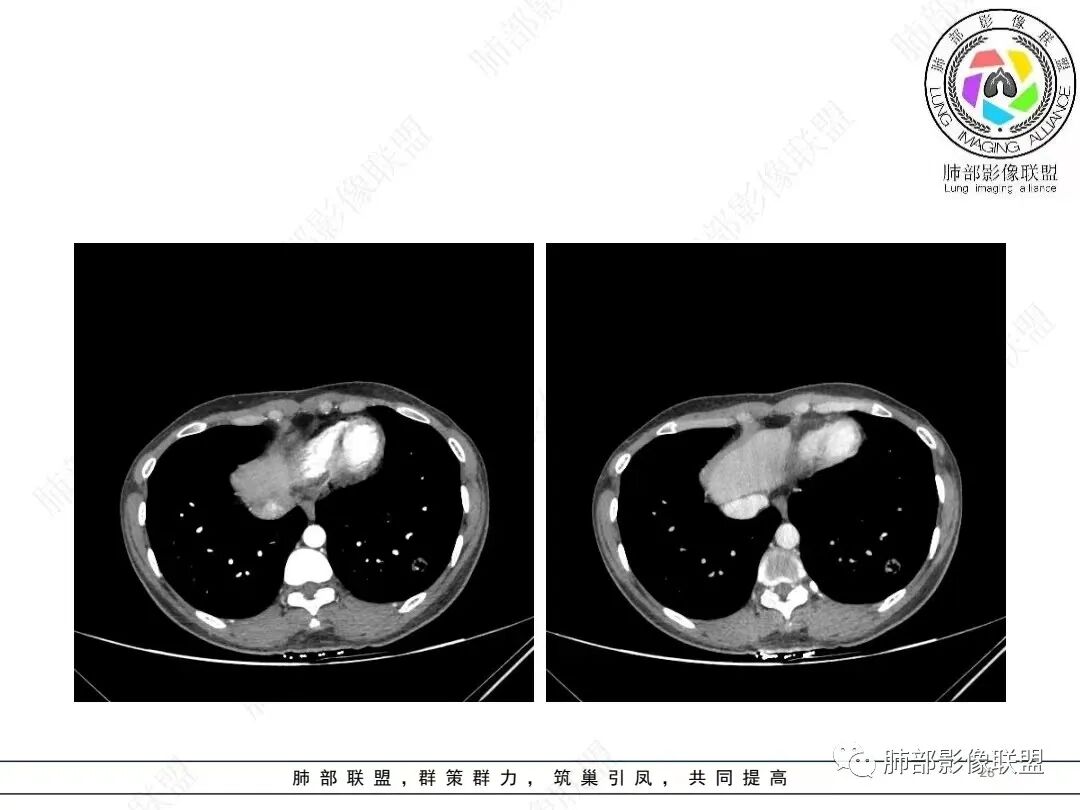

1、临床特点: 37岁女性,体检发现肺结节,2年前有甲状腺腺瘤手术史。实验室无阳性发现。

2、影像特点:左肺下叶类圆形结节影,周围可见多发细小毛刺,浅分叶,张力不高,未见胸膜牵拉。病灶内隐约见空泡影(未提供CT值),近端部分血管呈杵状增粗,可疑脐凹征。增强后实性部分有轻度强化。外围病灶,与支气管关系不明确。

4、病例小结:中青年女性偶然发现结节,表面欠光整,内部空泡,不均匀强化,边缘分叶毛刺等都具有影像学上的恶性征象,正如大多数老师所分析与肺腺癌较为符合。部分肺部肿瘤年轻化,尤其是肺腺癌等应当引发我们高度关注。